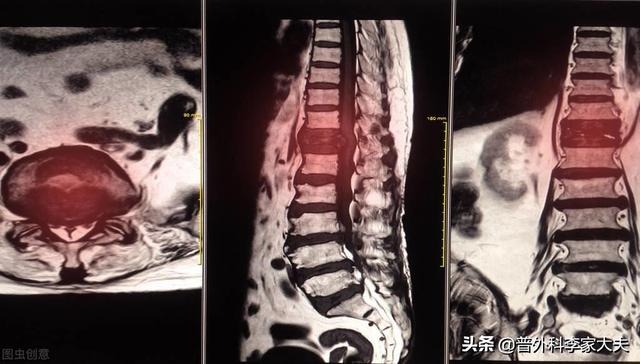

骨転移はどのような痛みに注意すべきですか?骨転移は悪性腫瘍の末期によく見られる症状で、体の他の部位にある原発腫瘍が血液やリンパ液の経路を通って骨に転移し、骨転移を形成することを指します。骨転移は、正常な骨組織が破壊され、腫瘍組織に置き換わっていることを示す。骨転移は病変の特異性により、溶骨型、造骨型、混合型の3つに分類される。骨転移の好発部位は中軸骨(脊椎、骨盤)、肋骨、下部骨幹部で、特に中軸骨が最も多く、これはこの部位の血液供給の特徴と関係しています。下の円のように骨転移が多発し、脊椎の状態が悪い。

骨転移の磁気共鳴画像法

胸椎に発生した骨転移性癌を示す。